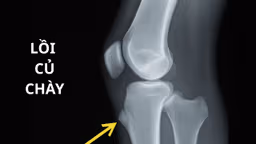

Trong một số trường hợp, việc tiến hành phẩu thuật để tái tạo hoặc thay thế khớp mới có thể giúp bệnh nhân duy trì cuộc sống bình thường hơn. Quyết định phẫu thuật thay thế khớp chỉ được thực hiện khi các biện pháp điều trị khác như thay đổi lối sống và dùng thuốc không còn hiệu quả nữa.